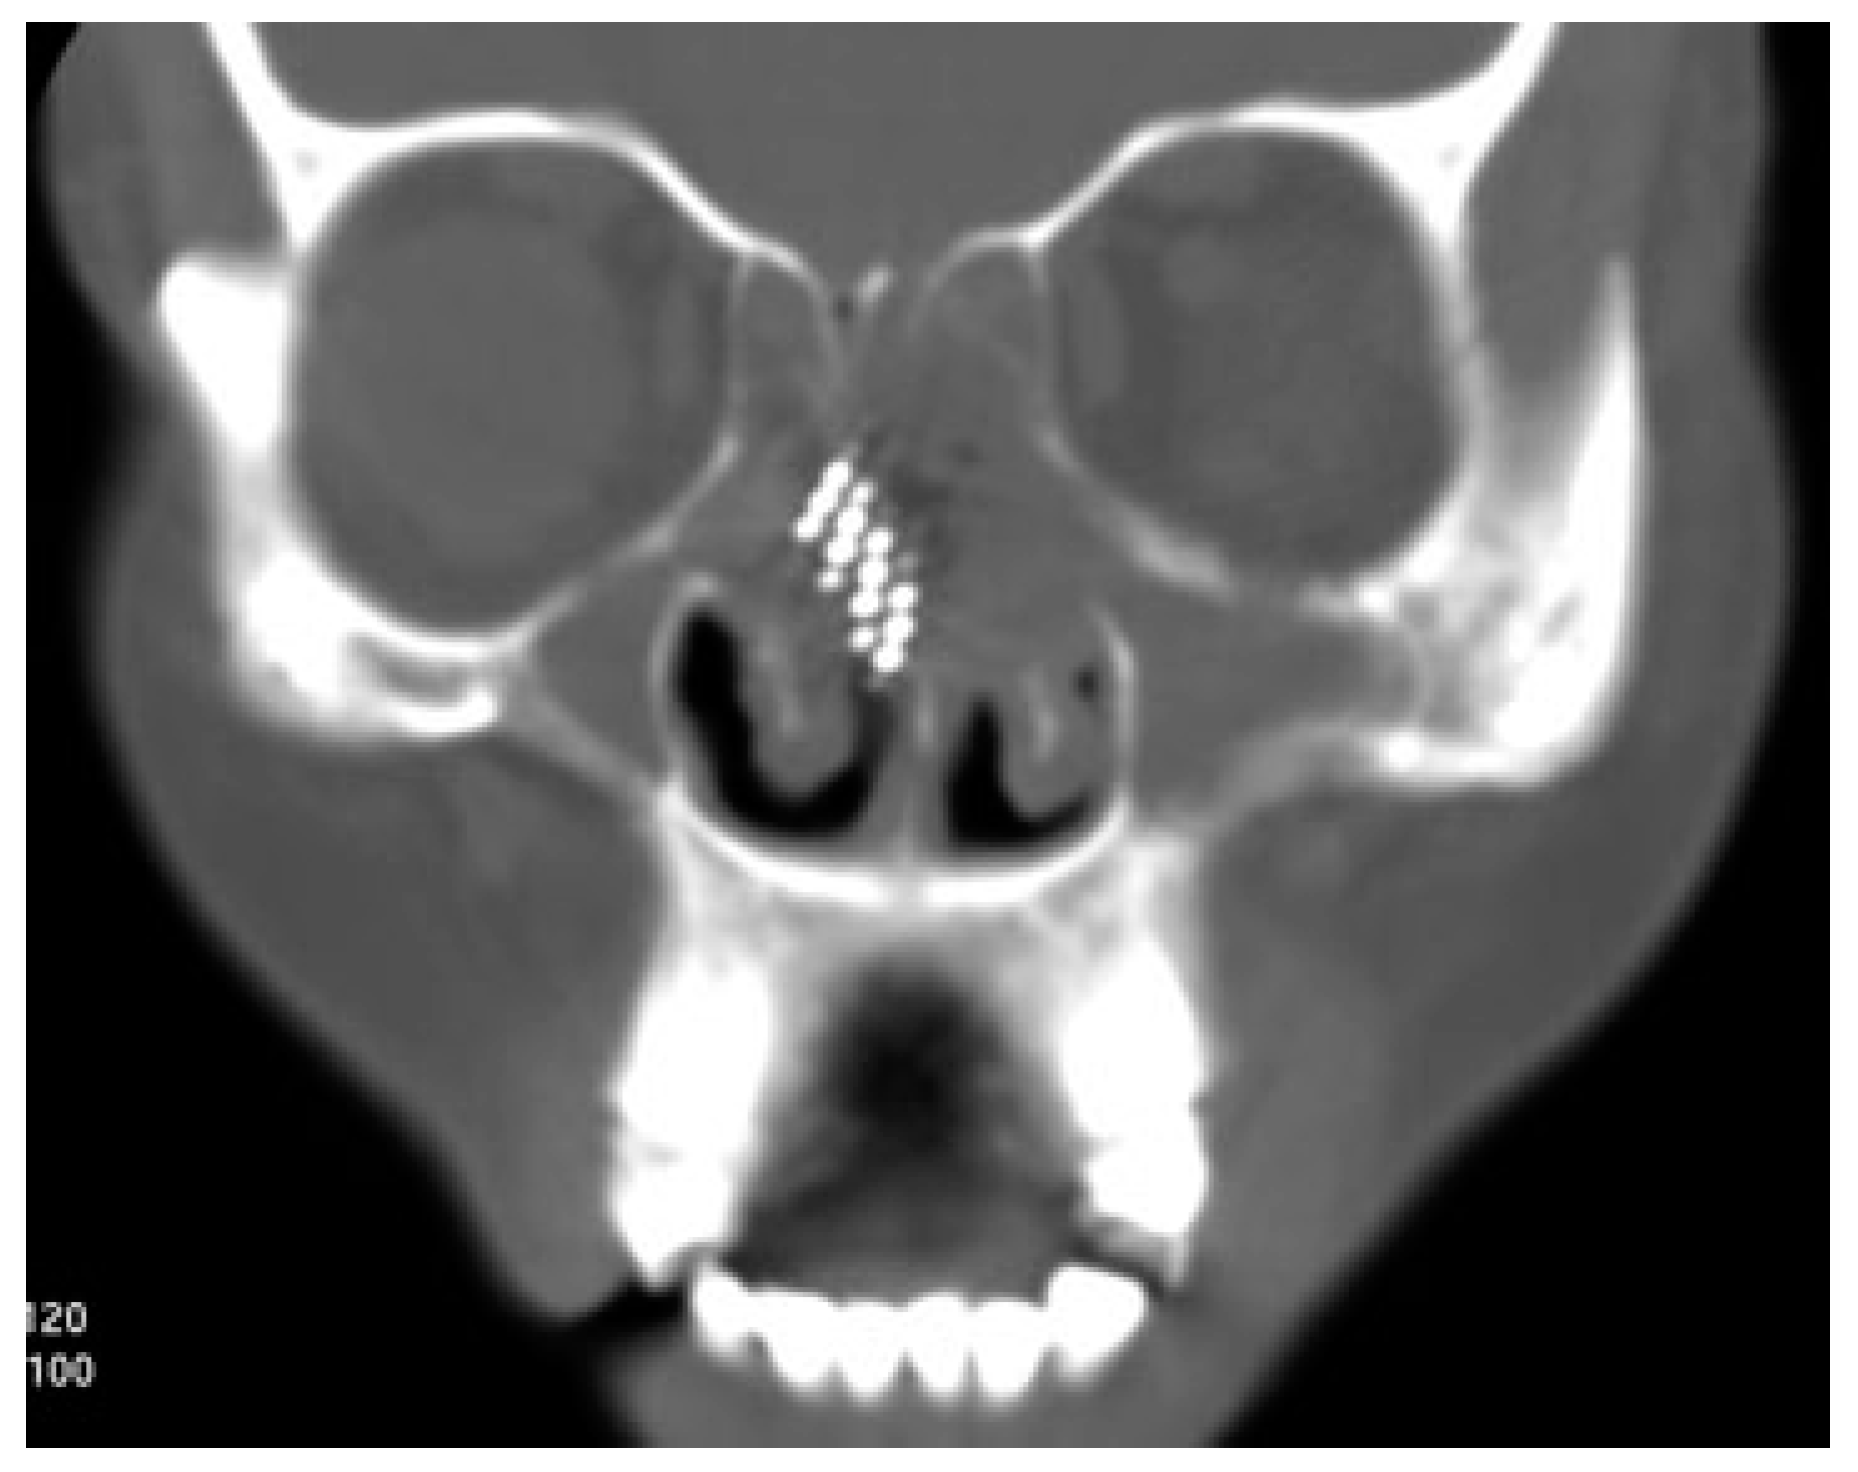

A 42-year-old woman reported to the Department of Oral and Maxillofacial Surgery with a toothbrush head lost in her nose. On careful elicitation of related events, we discovered that she had reportedly placed the tooth-brush into her nose to relieve herself of the irritable itching she was experiencing in her nose. She suffered from allergic rhinitis since childhood and frequently experienced nasal itching especially in the early morning hours. In this instance, she slipped on a wet floor and the resultant fall caused the tooth brush to snap into two pieces leaving the brush head inside the nose. The accident caused profuse nasal bleeding, which was controlled by the patient with finger pressure using a handkerchief. A computed tomographic (CT) evaluation was undertaken at a radiodiagnosis center (Figure 1) on the recommendation of a primary health care facility she had visited initially. An attempt was made at the primary health center to retrieve the brush head with a curved hemostat, which proved unsuccessful and led to a further episode of epistaxis. She was then referred to our center. She was brought to our department 3 hours after the accident. Visual inspection of the nasal cavity revealed right-sided vestibulitis with clotted blood in the right nasal cavity. The toothbrush head could not be seen on visual inspection with a nasal speculum and headlamp. Visual inspection of the pharynx was unremarkable. The patient did not complain of right nasal obstruction. The patient confirmed that she had not swallowed any portion of the object. The CT showed the presence of the toothbrush head in the superior right nasal cavity at the junction between the lateral and medial nasal walls. The brush head had caused a deviation of the nasal septum to the left (Figure 2). The patient was prepared for nasal endoscopy. The right nasal cavity was sprayed with a local anesthetic aerosol agent (lidocaine USP 15%, ICPA Health Products Ltd., Mumbai, India) and phenylephrine 0.25% applied on a cotton pellet. After 5 minutes, an endoscope was introduced into the right nasal cavity and showed a large wound in the upper part of the nasal cavity with clotted blood on the surface. No object could be identified in the nasal cavity. The patient was prepared for surgery under regional anesthesia. The patient was placed in a supine position with the head elevated ~20 degrees. The forehead, nose, and face were prepared with an antiseptic solution (2% cetavlon followed by alcohol). The nasal cavities were packed loosely with 1-cm ribbon gauze soaked in 4% lignocaine for 15 minutes. Anesthesia of the external nose was achieved using bilateral infraorbital nerve blocks (lignocaine 2% with 1:200,000 adrenaline, Xicaine, ICPA Health Products Ltd., Mumbai, India) with additional infiltrations at the base of the columella, the dorsum of the nose, the infratrochlear nerve, and the external nasal nerves, and about 0.5 mL of the solution was injected into the membranous septum. An open rhinoplasty approach with a transcolumellar extension was used. A marginal incision along the caudal border of the lateral crura of the lower lateral cartilages was made and carried medially and inferiorly along the cephalic border of the medial crus up to its lower part and then extended with a right angle turn to the caudal margin of the medial crus. A combination of sharp and blunt dissection was used to expose the entire nasal skeleton up to the nasal bones. The object was found to be lodged between the upper-right lateral cartilage and the nasal septum, with its bristles embedded into the right-upper lateral cartilage and the nasal septum (Figure 3). Dissection of the object from between the upper lateral cartilage and the nasal septum was performed after incising the upper-right lateral cartilage submucosally from the nasal cartilage and then proceeding with the exposure of the nasal septal cartilage. The object was delivered in one piece (Figure 4). Hemostasis was achieved with the use of electrocautery where indicated. Closure of the wound was achieved with polyglycolic acid 910 for the nasal mucosa and the nasal cartilages. Skin closure was achieved with prolene sutures. Bilateral nasal packs were placed. No intraoperative or postoperative complications were witnessed, and the patient was discharged on the third postoperative day.

Figure 2. Three-dimensional reconstruction of computed tomography images showing position of the foreign body.